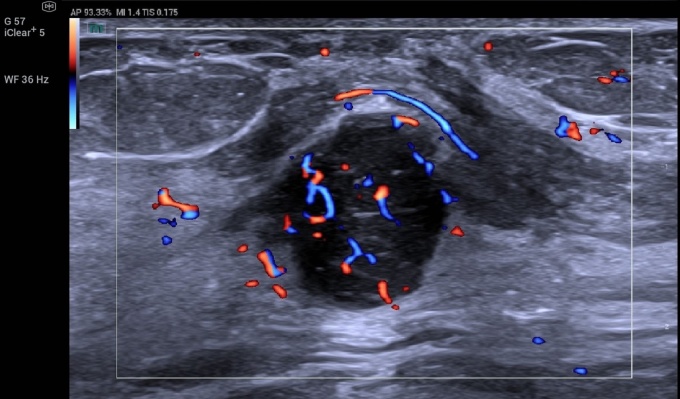

Another standout feature is Ultra Micro Angiography, which provides highly sensitive visualization of slow-flow microvasculature, often associated with vascular complications.

The system’s 500 fps super resolution mode was described as transformative by Prof. Dirk-Andre Clevert, Head of the Interdisciplinary Ultrasound Center, University of Munich–Grosshadern Campus.

“This gives us dynamic insight into tumor behavior and blood flow that would be missed in conventional contrast imaging,” Prof. Clevert noted. “It has the potential to redefine how we evaluate oncologic and transplant patients.”

“We can now see fine vessel structures, flow direction, and contrast arrival time—all within the same imaging session,” Prof. Clevert explained. “We’re talking about acquiring up to 15,000 frames of data per exam. That opens an entirely new perspective for ultrasound-based diagnosis.”